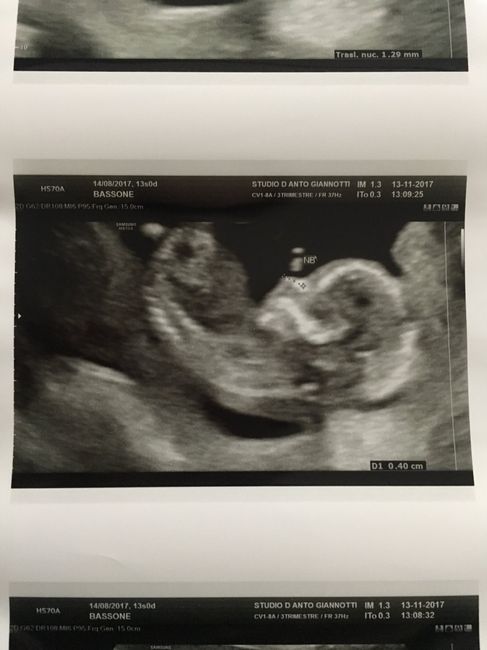

Per Vittoria ed Elisa....tolto mio marito ke bucava il monitor con lo sguarda x cercare un pisellino(abbiamo già una femmina!Smiley xd )non si è visto nulla....questa è l'eco!!!Era sui 5.5cm....

Future mamme maggio-giugno/2018 2